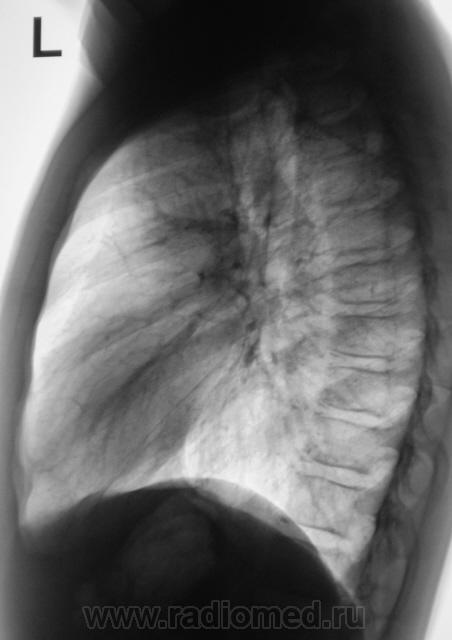

При расшифровке флюорограмм "взят на контроль". Подросток, первичная постановка на военный учёт. Жалоб нет.

Первая флюорограмма. Конечно, взяли на контроль. Разрезали. Сейчас выложу томограммы. Томограммы, как и всегда с "букетом роз".

А рентгенологически, что выставлять? Очаговый?

Два сегмента очаговый, больше двух диссеминир.

Конечно, ответственность, подросток и все такое... Но с другой стороны, кроме мелкого кальцинатика прицепиться больше не к чему. Все очаговоподобные тени видны при уменьшенной яркости и в местах пересечения сосуда с кортикалом ребра. Либо имеют "хвостик", что указывает на сосуд. Такое мое мнение.